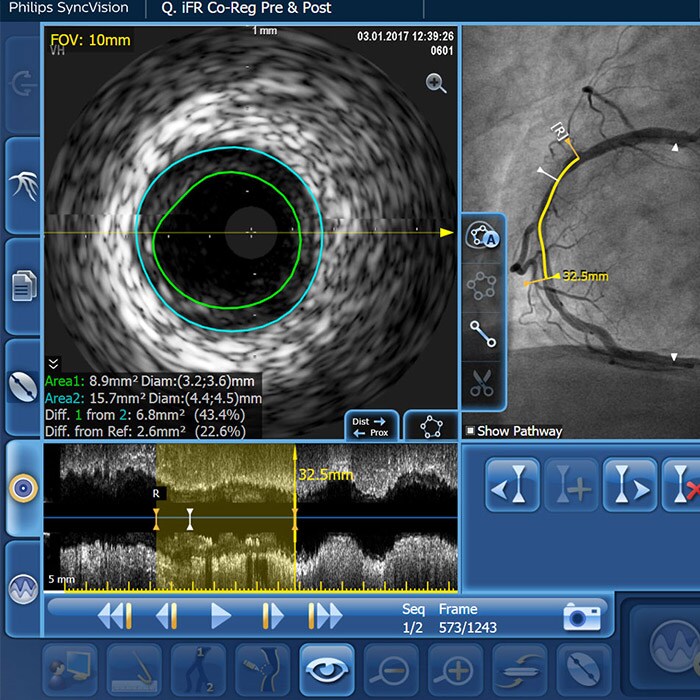

Saphenous vein graft and thrombus lesions

SVG patency rates have been reported at approximately 80% at 1 year and approximately 50% at 15 years and beyond.1

Clinical challenges

Advanced tools for optimal PCI outcomes